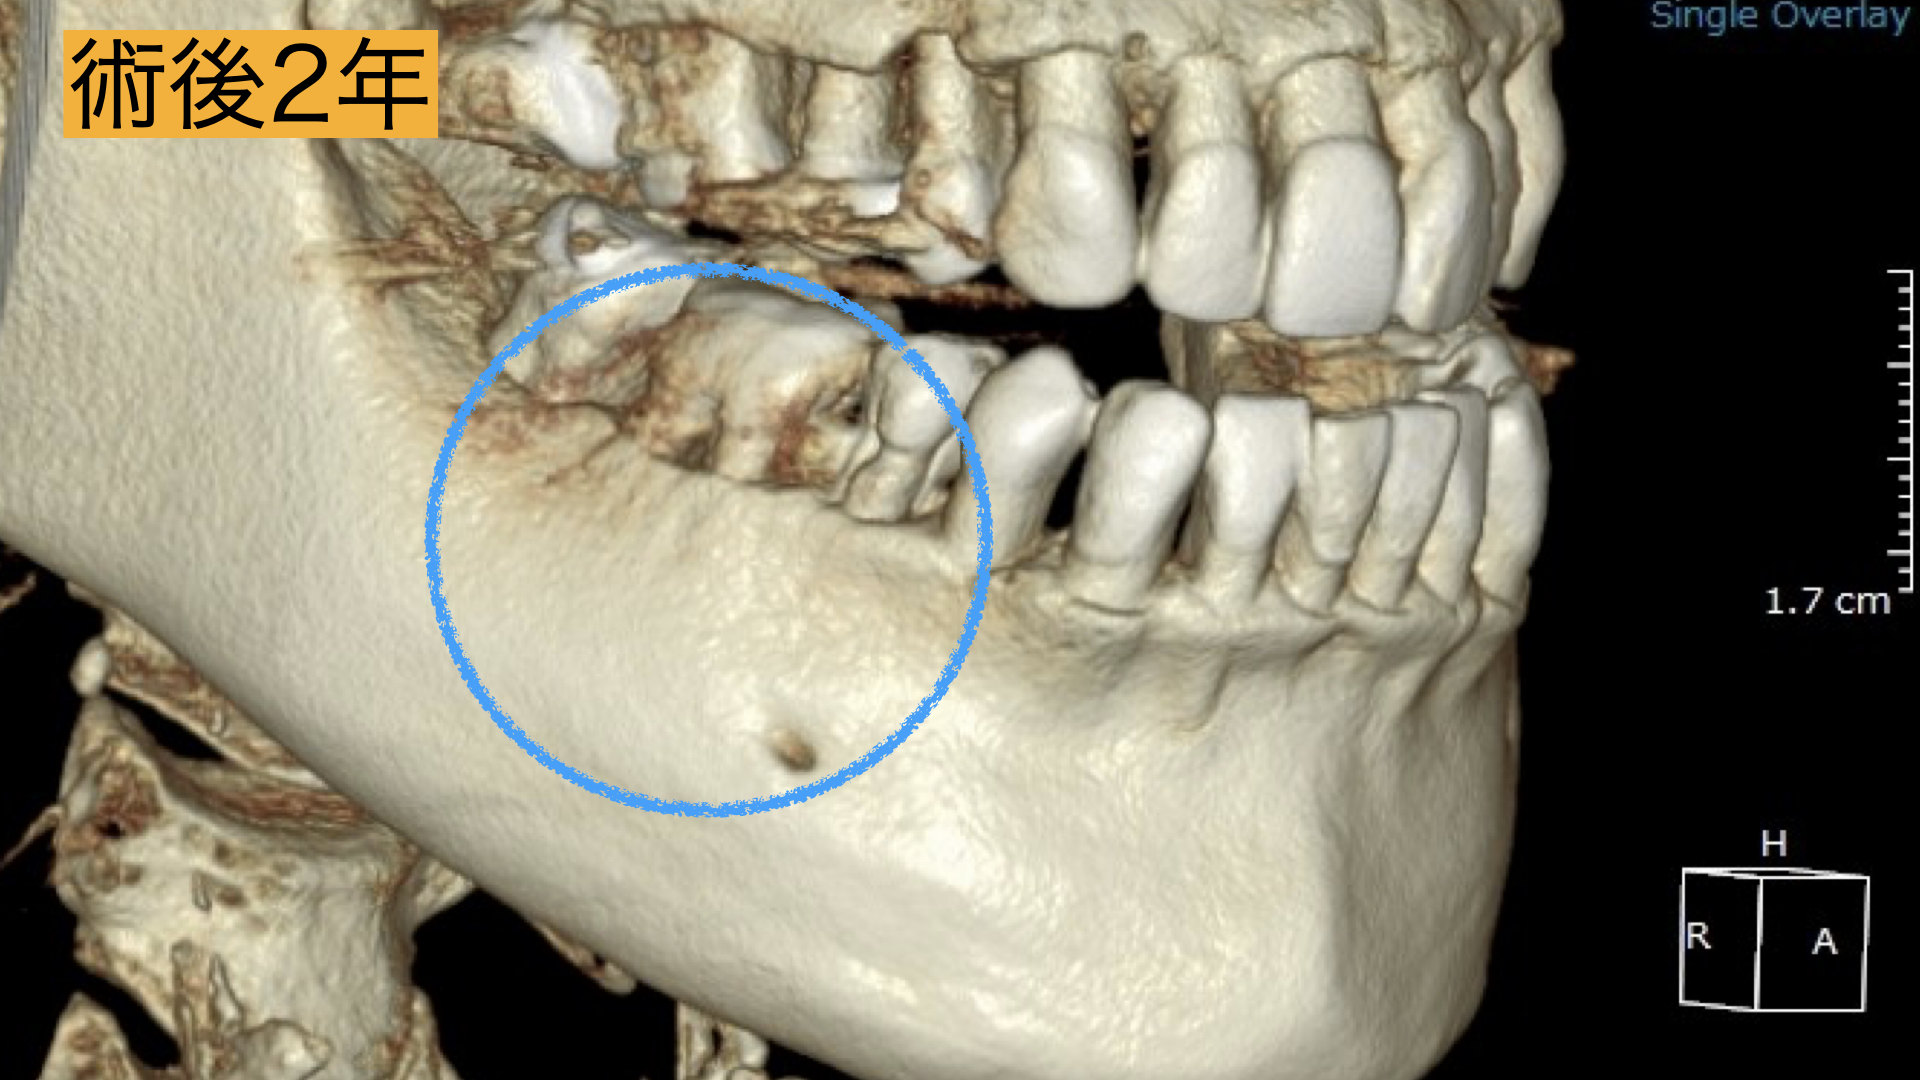

術後

術直後から痛み、腫れは、解消し2年間の経過観察も問題なく過ごせましたとのことでした。 レントゲンで骨の回復が確認とれ、非常に驚かれておりました。